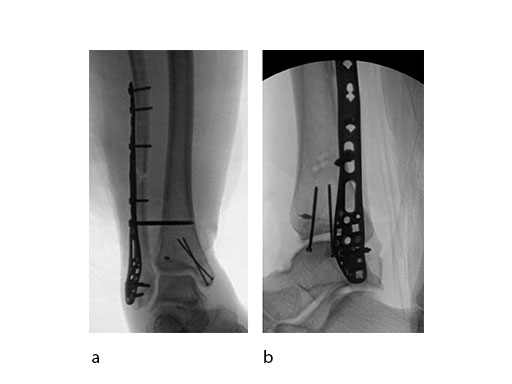

A 45-year-old patient fell from his horse, receiving a closed bimalleolar fracture/ dislocation (Fig 10). Computed tomorgraphy demonstrated an additional anterolateral avulsion injury and syndesmosis dislocation. Osteosynthesis was conducted with a VA-LCP Lateral Distal Fibula Plate.

Push technique was required to achieve fibular reduction, and the syndesmosis was reduced and clamped with periarticular clamps (Fig 11). Postoperative x-rays at 4 weeks demonstrated good maintenance of reduction (Fig 12).